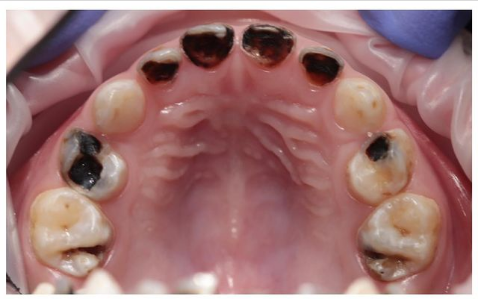

О стоматологе

Елена Александровна детский стоматолог ведет активный образ жизни и развивает свой блог в Инстаграм о детской стоматологии @dr_butina, регулярно занимается спортом, обожает семейные прогулки и готовить десерты! Лечение кариеса, пульпита, периодонтита молочных и временных зубов, удаление временных зубов, герметизация фиссур, восстановление разрушенных зубов коронками, помощь при травме зубов. Елена Александровна прекрасно адаптирует маленьких пациентов к лечению, сотни положительных отзывов родителей тому подтверждение, проводит великолепную адаптацию для детей с негативным опытом лечения зубов. Лечение детей с сопутствующими патологиями. Проводит комфортное, грамотное лечение маленьких пациентов в седации (закись азота) и в условиях общего обезболивания (в наркозе).

Бутина Елена Александровна: портфолио (8)